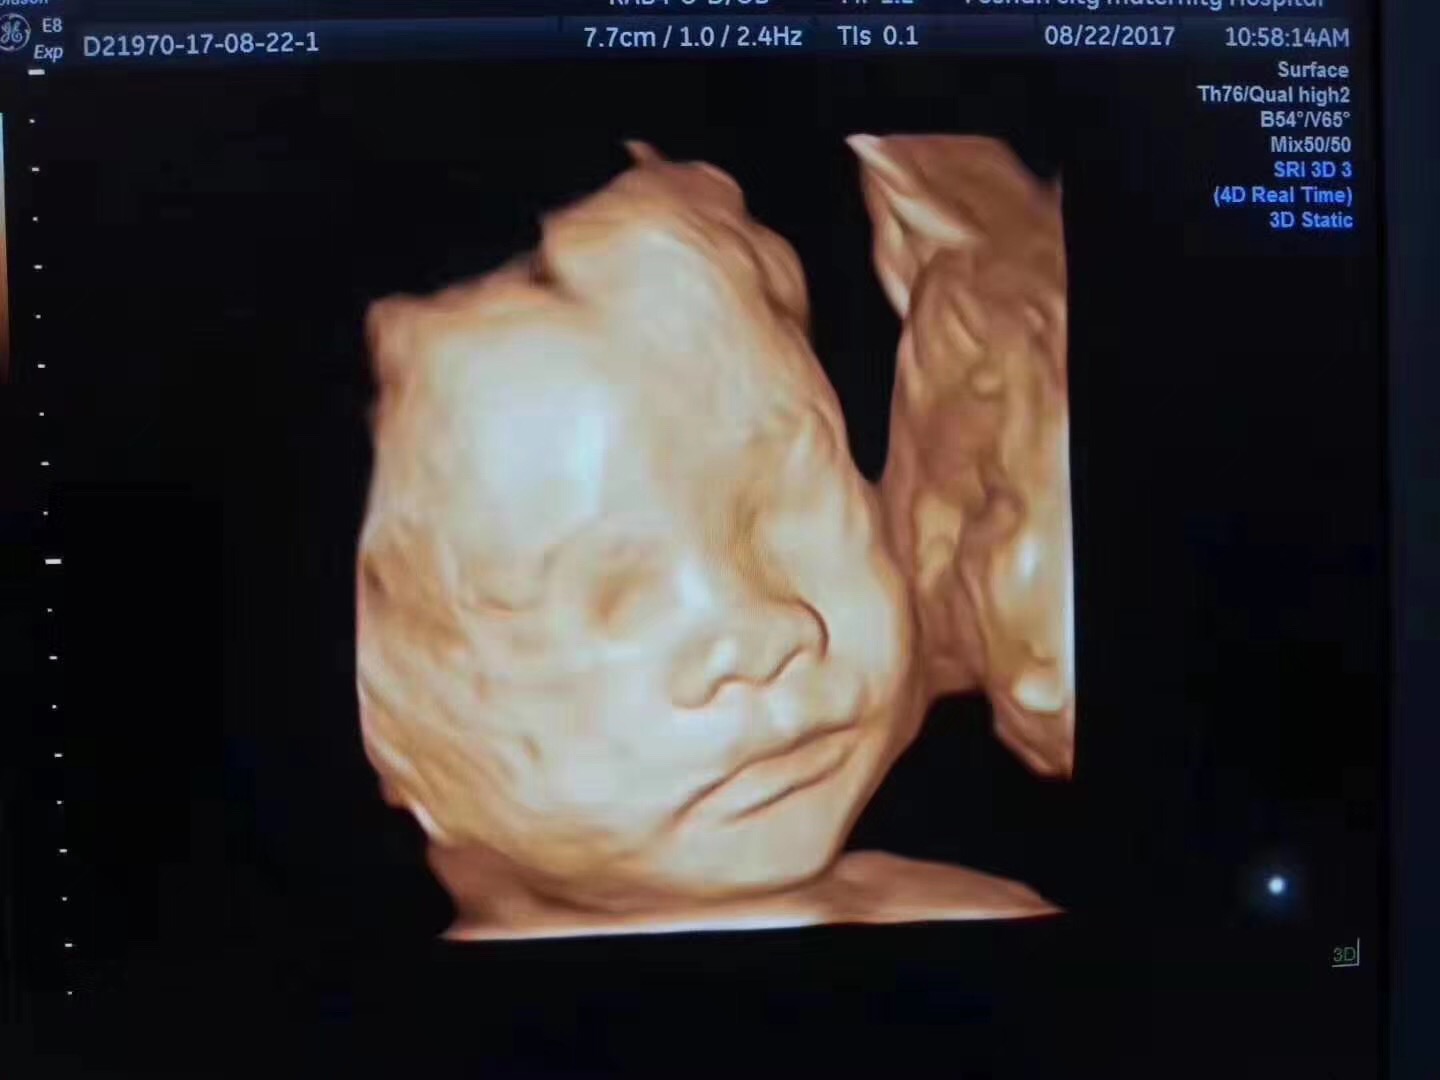

孕期四维彩超,你了解的有多少?

四维彩超能检查什么?

四维彩超检查为筛查胎儿先天性体表畸形和先天性心脏疾病提供准确的科学依据,以便尽早发现尽早干预。

为了让宝爸宝妈们更加清楚地了解胎儿的发育情况,佛山都市妇产医院四维彩超检查由多年临床经验的超声医生进行检查,副主任医师以上进行报告解答,为宝宝的健康保驾护航。

做超声影像(四维彩超)的合适时间?

适宜检查时间:单胎是孕22-26周,双胎是孕20-24周。因为胎儿在24周左右正是大脑突飞猛进的发育时期,这个时期的胎儿结构基本形成,胎儿大小以及羊水适中,在宫内活动空间比较大,胎儿骨骼回声影响较小,图像也比较清晰。